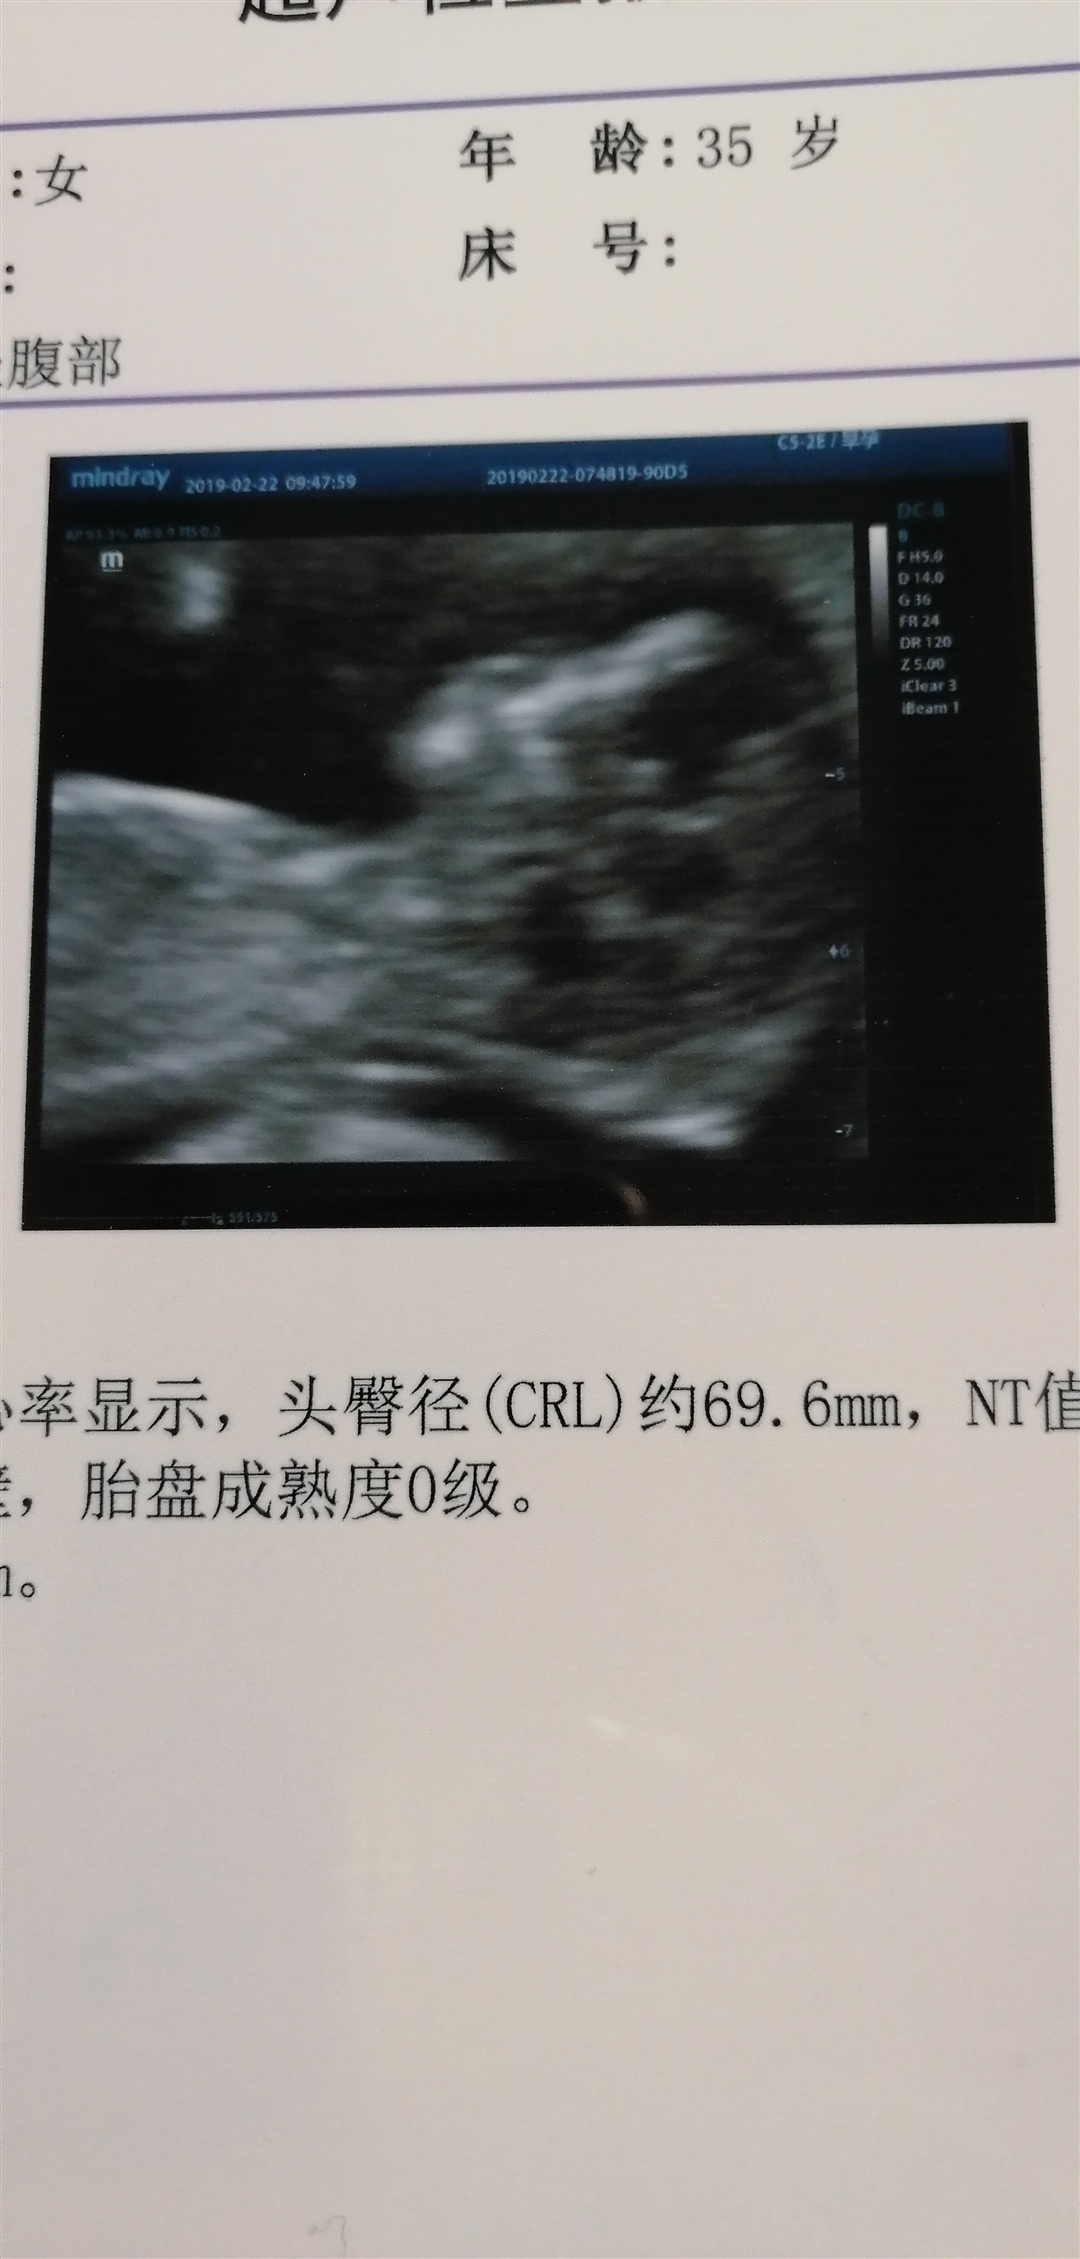

我感觉会看这个的都是最强大脑,到底是男是女